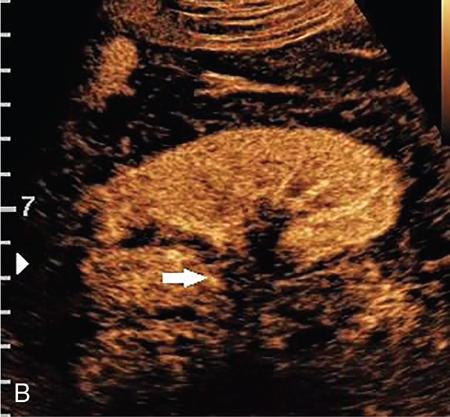

Drushi Patel CONTRAST-ENHANCED ULTRASOUND IN ADULT GENITOURINARY IMAGING Mridula Muthe Ultrasound is the initial screening examination for the evaluation of the renal morphology and suspected renal lesions due to its multiple advantages such as easy accessibility, bedside assessment, affordability and lack of radiation. Vascularity of the kidney and renal lesions can be studied with the use of colour Doppler ultrasound however, it provides information only about the macrovasculature. With the use of microbubble ultrasound contrast agents (UCAs) macro as well as the microvasculature can be studied. Contrast-enhanced ultrasonography (CEUS) is also more sensitive than Doppler ultrasound as it is not affected by blood velocity and angle of insonation of the ultrasound beam. In urology, the established applications of CEUS in adults include characterization of cystic lesions and differentiation between pseudotumours and solid lesions. Box 10.23.1.1 provides a list of European Federation of Societies for Ultrasound in Medicine and Biology (EFSUMB) recommended indications of CEUS in renal evaluation. EUROPEAN FEDERATION OF SOCIETIES FOR ULTRASOUND IN MEDICINE AND BIOLOGY (EFSUMB) RECOMMENDED INDICATIONS FOR USE OF UCA IN RENAL EVALUATION Renal ischaemia. Evaluation of solid renal lesions. Differentiation between solid renal lesions and pseudotumours. Characterization of complex cystic masses. Characterisation of indeterminate renal masses. Renal infections. Follow-up of nonsurgical complex masses. To improve lesion visualization in patients undergoing renal tumour ablation under US guidance and to detect residual tumour either immediately or after ablation. Isolated blunt moderate-energy renal trauma. Follow-up of trauma patients managed conservatively. Characterization of thrombus in renal vein and inferior vena cava. In patients with contraindications for CT- and MRI-based contrast media. Evaluation of lesions in transplant kidneys. Evaluation of ischaemia and vascular complications in transplant kidneys. Tumour response assessment to biologic therapy. Intracavitary CEUS for guiding percutaneous nephrostomy. Source: P.S. Sidhu, V. Cantisani, C.F. Dietrich, O.H. Gilja, A. Saftoiu, E. Bartels, et al., The EFSUMB guidelines and recommendations for the clinical practice of contrast-enhanced ultrasound (CEUS) in non-hepatic applications: update 2017 (long version). Ultraschall in der Medizin-Eur. J. Ultrasound 39 (02) (2018) e2–e44. CEUS involves the intravenous injection of UCAs consisting of gas microbubbles. These UCAs remain purely in the intravascular compartment as they are small enough to avoid filtration by the lungs and too large to enter the interstitial compartment. UCAs cause marked amplification of signals from the flowing blood, thus providing information about the microvasculature and parenchymal perfusion. Sonovue is a second-generation UCA and is the only UCA available in India. It consists of sulphur hexafluoride gas which is exhaled by the lungs and is surrounded by phospholipid monolayer which is metabolised by the liver, making it safe for patients with renal insufficiency. For renal evaluation, a dose of 1–1.5 mL of Sonovue is administered as a bolus dose followed by a 10 mL saline flush. CEUS is performed on machines with contrast-specific software’s using a low mechanical index (MI) technique. The use of a dual image display is beneficial for the evaluation of small lesions. A conventional B-mode ultrasound is first performed to acquire measurements, assess morphology and to detect focal lesions along with Doppler ultrasound to assess vasculature. However, due to limitations in the assessment of focal lesions, microvasculature, complex cysts, poor contrast between the lesion and cortex or medulla, it is preferable to perform a CEUS study for additional characterization. The enhancement pattern of the kidney is different than that of the liver due to the dual blood supply of the liver as opposed to afferent arterial supply and efferent venous drainage of the kidney. After an intravenous bolus of UCA, kidneys show intense enhancement. Contrast is first seen in the main renal artery, followed by its branches. CEUS has only two enhancement phases, that is cortical phase which lasts for 15–30 seconds and a parenchymal phase (enhancement of both cortex and medulla) for 25 seconds–4 minutes after UCA administration. The renal cortex enhances first, followed by the outer medulla which is followed by gradual enhancement of the pyramids (Fig. 10.23.1.1). During the washout phase first, there is a reduction in the medullary enhancement followed by a slower washout of the cortex. As kidneys don’t excrete UCAs, there is no opacification of the pelvicalyceal system. UCAs can act as a problem-solving tool in patients with renal failure as they are not nephrotoxic. Due to its excellent ability to depict renal vascularization, it can be used for detecting perfusion abnormalities. CEUS is useful for detecting vascular causes of renal function deterioration. Renal infarcts appear as wedge-shaped nonenhancing areas in all phases. Renal infarcts show a focal complete lack of parenchymal enhancement on CEUS whereas ischaemic areas show reduced enhancement. CEUS can confidently differentiate infarction from cortical necrosis by the demonstration of preserved hilar vascularity in the latter. Renal pseudotumours such as foetal lobulations, dromedary hump, parenchymal hypertrophy due to renal scarring and column of Bertini can be accurately differentiated from true tumours using CEUS. Pseudotumours show similar enhancement to the adjacent parenchyma and appear isoechoic on all phases while true tumours show different enhancement pattern on at least one phase (Fig. 10.23.1.2). True tumours will cause mass effect and distort the normal vascular architecture of the renal parenchyma whereas in pseudotumours the vascular architecture is preserved. In addition, the identification of medullary pyramids within the mass points towards it being a pseudotumour rather than a true mass. Cysts can be categorized according to the Bosniak classification using CEUS. Due to its superior spatial and temporal resolution, CEUS is considered superior to CT for detecting additional septations, wall or septal thickening and solid components (Figs 10.23.1.3–10.23.1.5). CEUS allows for real-time imaging of blood flow within the septae, wall or nodules within the cysts which may not be seen on CT or MR imaging. The sensitivity of CEUS is comparable to CT for the classification of renal cystic lesions as benign or malignant however, it is not as useful for staging. The follow-up of inoperable complex cystic lesions is better performed with CEUS rather than CT due to the absence of ionizing radiation. Complex cysts or masses with calcifications are not suitable for evaluation with CEUS. CEUS allows a detailed evaluation of the circulation in mass lesions as it demonstrates the macro as well as microvascular enhancement patterns. CEUS has more sensitivity than CT for detecting blood flow in hypovascular lesions. It can also be used to distinguish between complex cysts and solid lesions which remain equivocal on CT and ultrasound (B-mode and colour Doppler). CEUS is sensitive in identifying cystic areas, necrosis, debris and haemorrhage in small tumours that may be difficult to visualize on CECT and MR. Isoechoic lesions on conventional ultrasound are better characterized by CEUS (Fig. 10.23.1.6). Hyperdense renal lesions on noncontrast CT (NCCT) with HU values between 20 and 70 are better evaluated by CEUS which can classify these lesions as solid or cystic. CEUS can suggest the histological subtype of tumours. Clear cell carcinomas show heterogeneous hyperenhancement in the cortical phase and rapid washout along with a peripheral enhancing rim or pseudocapsule seen during the parenchymal phase. Papillary carcinoma shows progressive heterogeneous enhancement during the cortical phase and displays hypoenhancement as compared to the cortex on all phases. Malignant renal vein thrombus will show enhancement as compared to bland thrombus on CEUS. Tumours that are smaller than 3 cm commonly show homogeneous enhancement, regardless of their histologic subtype. Differentiation between angiomyolipoma, renal cell carcinoma and oncocytoma is not always possible. Although, CEUS has excellent sensitivity for the detection of malignancy, it has a higher false-positive rate as compared to CECT. Hence, combined use of CEUS for its high sensitivity and CECT for its high specificity may be performed for an accurate diagnosis. CEUS is effective in patients with complicated pyelonephritis, for identifying inflammatory parenchymal involvement, characterized by round or wedge-shaped hypovascular parenchymal areas, most conspicuous during the late parenchymal enhancement phase. An abscess is seen as a nonenhancing area, with or without peripheral or septal enhancement. CEUS can also be used for the follow-up of renal abscesses. All the aforementioned indications of CEUS in native kidneys also apply to renal transplants. Infarction, vascular complications such as arterial and venous thrombosis can be detected. Quantitative CEUS for assessment of graft dysfunction is a subject of active research. CEUS can be used as an alternative to CT especially in children with isolated blunt moderate energy injuries who are hemodynamically stable. It can also be used in the follow-up of conservatively managed trauma patients and in renal impairment. During Focused Assessment with Sonography for Trauma (FAST), the examination should begin with the kidneys as they have a fleeting enhancement. The kidneys are studied in the arterial phase with two separate doses administered for either kidney during FAST. On CEUS, lacerations, hematomas, and infarcts are seen as nonenhancing areas on late-phase images whereas contusions may show faint enhancement. Pseudoaneurysms and active bleeding are diagnosed on the arterial phase. Crucial complications such as devascularized parenchyma and acute cortical necrosis can also be diagnosed on CEUS. Pelvicalyceal system injury cannot be detected by CEUS as UCAs are not excreted by the kidneys. CEUS can be performed in conjunction with percutaneous ablation therapies. Preablation evaluation with CEUS is essential to assess lesion vascularity and to compare pre and postprocedure tumour viability. Also, the identification of a pseudocapsule predicts improved ablation efficacy. CEUS has demonstrated high sensitivity, specificity and accuracy for the early detection of residual unablated tumour. Dynamic contrast-enhanced ultrasound is a useful tool for early identification of responders and nonresponders, enabling tailoring of the treatment regimen. It is performed by two methods – Bolus injection of a UCA with time-intensity curve analysis (commonly used) and intravenous injection of UCA with disruption–replenishment analysis. In patients with chronic kidney disease, the contrast enhancement is less intense and fades earlier as compared to a normal kidney. CEUS aids in characterizing renal lesions in patients with renal failure. Characterization of lesions with indeterminate appearances in patients with renal dysfunction, on conventional US prevents unnecessary further evaluation with contrast-enhanced CT or MRI and further deterioration of the renal function as well as unwarranted investigations. CEUS nephrostomogram can be performed after percutaneous nephrostomography to confirm the correct positioning of its tip, detect the site of obstruction and to diagnose complications. UCAs can be safely administered in patients with minimal risk. They can be safely administered in patients with renal insufficiency as they are not excreted by the kidneys. Prior laboratory tests are not indicated as they are not nephrotoxic and don’t interact with thyroid function. Most adverse effects are mild such as nausea, headache, chest discomfort, chest pain and resolve spontaneously. The contraindications include known hypersensitivity, patients with right-to-left shunts, severe pulmonary arterial hypertension (pulmonary arterial pressure >90 mm Hg), uncontrolled systemic hypertension, and respiratory distress. The rate of anaphylactic reactions is significantly lower than iodinated contrast media and comparable to gadolinium-based contrast agents. Caution should be exercised in patients with severe acute coronary disease and in patients with unstable angina. CEUS is a rapidly evolving technique, can be conveniently performed as an extension of conventional ultrasound and acts as a valuable tool in the characterization of indeterminate renal lesions, especially when the lesion is small. The advantages of CEUS include quick assessment, real-time imaging, high contrast resolution, excellent safety profile, lack of ionizing radiation, great repeatability, and most importantly, ideal for contrast evaluation in patients with deranged renal function. DUAL-ENERGY AND SPECTRAL IMAGING IN GENITOURINARY SYSTEM Aditi Chaitanya Gujarathi-Saraf Dual-energy CT (DECT) also known as ‘spectral imaging’, was first conceptualized in the 1970s. However, the clinical applications of DECT have recently emerged as owing to improvements in postprocessing techniques. The development of a single-detector, single-source DECT (ssDECT) with the capability for rapid alternation between two peak voltage settings (‘fast switching’) and a dual-detector, dual-source DECT (dsDECT) system in last few years have made possible various applications in solving clinical problems. In DECT, the simultaneous use of two different X-ray beam energy settings (80 and 140 kVp) allows the differentiation of materials on the basis of their attenuation characteristics (material density). There are two major applications of DECT in genitourinary system. First being characterization of renal calculi to differentiate those containing uric acid (UA) from those which do not. The other application is to characterize small renal masses which include differentiating complex cysts from renal tumours, detection of solid growth in PCKD patients and detection of residual tumour after thermal ablation of a renal neoplasm. The principle of DECT imaging is based on the differential absorption of X-ray energy at variable kVp settings. In DECT, two energy levels (typically 80 and 140 kVp) are used to acquire images that can be processed to generate additional datasets. Thus, a tissue or any material in the body shows different degrees of attenuation when scanned at different X-ray energies. Conventional CT numbers (attenuation measurements in Hounsfield units) are related to the linear attenuation coefficient of a particular material. The unique linear attenuation coefficients obtained by imaging at two different energies can be used to discriminate between different materials (e.g. fat, calcium, iodine and water). The characterization of material on DECT depends on their CT number ratio (CTR) also called dual-energy ratio. DE RATIO = CT number of a given material in the low-energy image CT number of the same material in the high-energy image DECT and spectral CT can be performed by three techniques (Fig. 10.23.2.1): Two sets of material-specific images are created to detect the presence or absence of a material. The two basic materials selected should have significant difference in mass attenuation coefficients and atomic number. The two commonly selected pairs are: Iodine-specific images are most commonly used in the clinical practice. When iodine is paired with water, two separate image data sets are generated. On water density image, the voxels that show change in attenuation due to presence of iodine are removed. These are instead represented on iodine density images. Thus, virtual unenhanced images are generated which resemble the conventional unenhanced images. Renal calculus disease is a common disease affecting approximately 10%–14% of population in India commonly affecting 31–45-year-old patients. Accurate diagnosis of composition of renal calculi is crucial as the frequency of prevalence and recurrence rate of renal calculi is high in most states of India. The obstructing calculi can lead to obstructive uropathy, pyelonephritis, urinary sepsis with nearly 50% of the patients being affected by renal failure. There are multiple compositions of renal calculi, most common being calcium oxalate (70%), calcium phosphate (20%), uric acid (8%) and cystine (2%). In general, UA calculi have lower attenuation values than nonuric acid calculi (i.e. struvite, cystine and calcium) on conventional CT. However, it may be difficult to distinguish between the two due to overlap in attenuation values. Here DECT becomes a problem-solving tool as it uses the two-material differentiation approach. Thus, in addition to size and location, DECT provides information about the composition of calculi to the urologist. DECT has high sensitivity of 88%–100% and high accuracy of 93%–100% to differentiate UA calculi from nonuric acid UA calculi. This is of utmost clinical importance as UA calculi can be treated medically whereas non-UA calculi require invasive methods of treatment such as extracorporeal shockwave lithotripsy (ESWL) or percutaneous nephrolithotripsy (PCNL). In clinical practice, NCCT scan of KUB region is performed at 80 and 140 kVp to generate two image datasets and obtain the DE ratio. A cut-off value of DE ratio of 1.2 is used to differentiate UA calculi from non-UA calculi (Fig. 10.23.2.2). Following flow chart shows differentiation of renal calculi based on DE ratio.